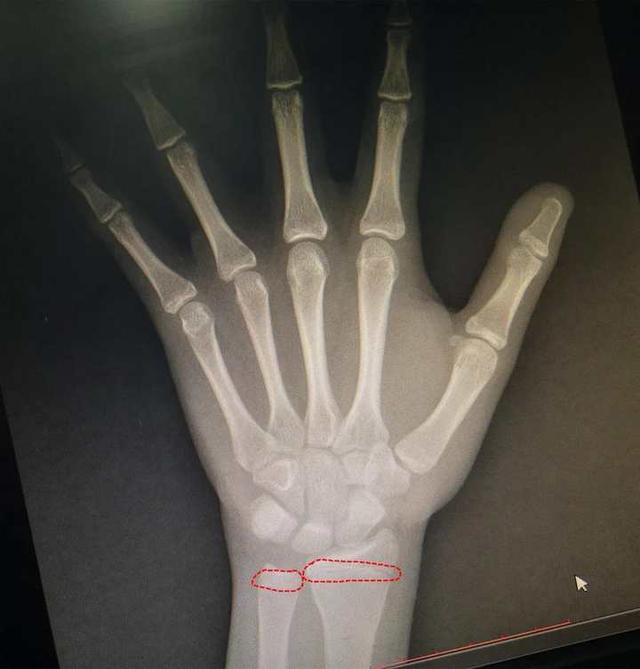

13岁男孩(小振) , 1米6多 , 体重140斤 , 看起来就和大小伙子差不多了 , 最近妈妈带着他来医院检查下 , 看看还能长多高 。 结果骨龄片子拍出来一看:糟糕!骨骺马上要闭合了 。

13岁小振的骨龄片

“也就是说 , 已经几乎没有长高的空间了!”树兰(杭州)医院儿科主任覃珍主任医师介绍 , 原本按照孩子父母的身高 , 小振的身高能长到172cm , 但是肥胖导致他提早发育 , 提前透支了他的生长空间 。